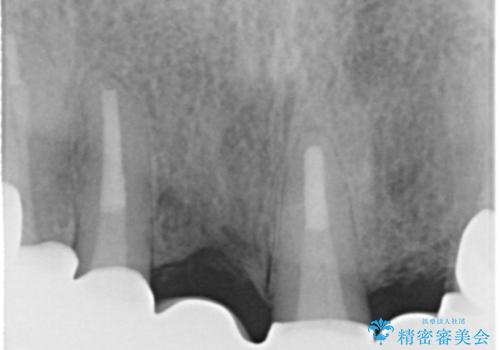

- 若い時に作った前歯のブリッジがの根元が黒くなってきているとのことで来院。

支える歯が1本虫歯がひどく、割れていました。

根の治療からやり直して新しいブリッジにしています。

ブリッジの支台歯は、根の再治療を含めて行なっています。